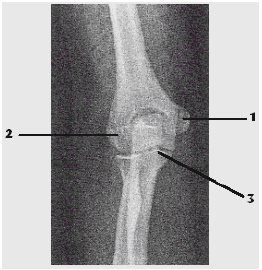

Observe a imagem radiográfica abaixo e assinale a alternativa que apresenta

corretamente

as estruturas assinaladas.

1-epicôndilo medial; 2-epicôndilo lateral; 3-processo coronóide.

1-epicôndilo lateral; 2-epicôndilo medial; 3-processo coronóide.

1-epicôndilo medial; 2-epicôndilo lateral; 3-processo coracóide.

1-epicôndilo lateral; 2-epicôndilo medial; 3-processo coracóide.